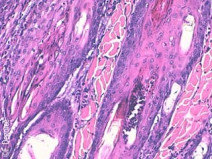

• Journées de pathologie clinique du GEDAC

Le Groupe d’Étude en Dermatologie vous propose la première édition des Journées spécialisées de Pathologie Clinique.S'intéressant aux dermatoses éosinophiliques et neutrophiliques, elles seront l'occasion de développer les aspects cliniques mais aussi diagnostiques (avec un accent tout particulier sur la cytologie et l'histopathologie) et thérapeutiques d'entités souvent mal connues ou reconnue...